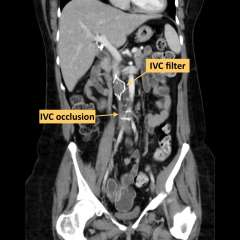

X-Ray diagram of IVC occlusion and filter

• IVC Occlusion:

When clot around the IVC filter remains there for an extended period it can lead to a complete permanent blockage of the IVC, also known as IVC occlusion. This leads to long term leg swelling, pain and immobility